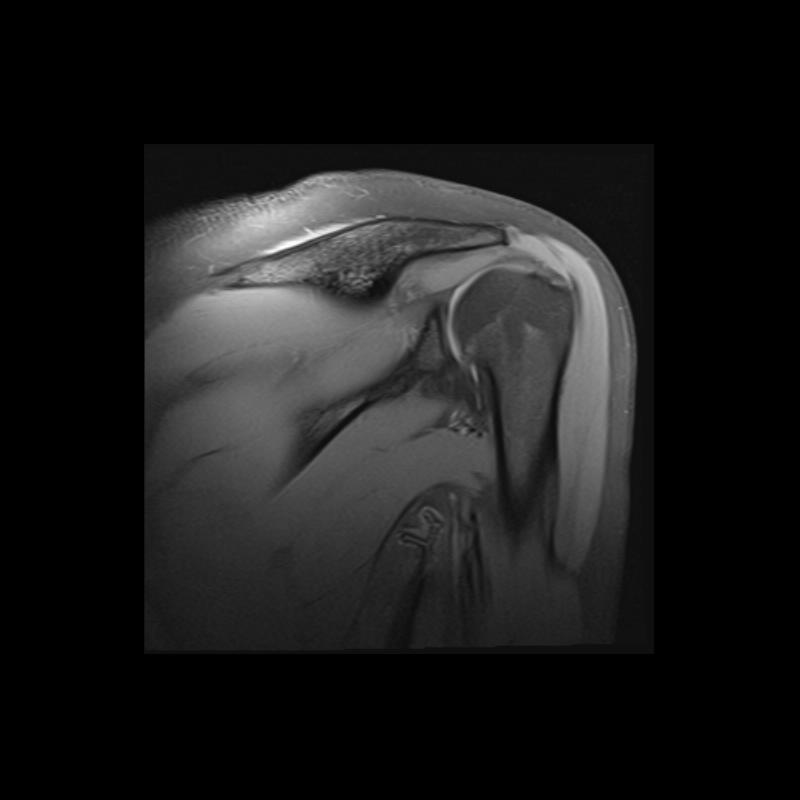

Shoulder MRI Anatomy